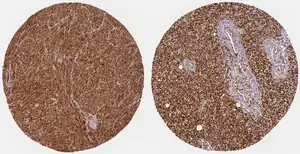

Cancers

WWTR1 (TAZ) is implicated a wide variety of cancers including melanoma, head and neck squamous cell carcinoma, breast cancer, non-small cell lung cancer, and others due to its high gene and histological expression, as well as correlation with increased metastasis and poorer survival in animal studies and patient data.[9] Along with the structurally similar co-regulator YAP, many studies have described their role in promoting oncogenesis, altering neoplastic metabolism, and generating resistance to therapeutic intervention.[8][9][32][33] In particular, TAZ overexpression conferred resistance to cisplatin chemotherapy as well as immunotherapy treatment with a PD-1 antibody.[32]